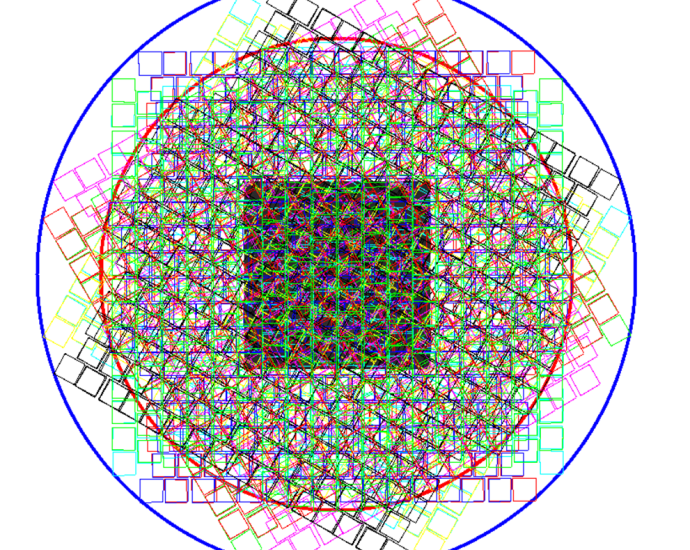

‘Backward and upward and tilted’: Spaceflight causes astronauts’ brains to shift inside their skulls

What effects do spaceflight have on the astronaut brain? (Image credit: Wang, Odor, et al.) Spaceflight doesn’t just change your perspective — it shifts the actual position of your brain inside your skull, a new study reports. Many of us know about the famed ” overview effect, ” which describes how a trip to theContinue Reading